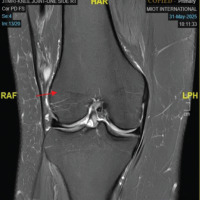

Radiographs demonstrated a subtle radio-opaque circular shadow located just posterior to the tibial slope (Fig. 1). T2-weighted MRI imaging revealed a well-defined lesion with heterogeneous signal intensity, measuring 1.4 × 2.5 × 3 cm. The lesion was situated in the midline posterior compartment, anterior to the knee capsule, and in close proximity to the posterior cruciate ligament (PCL) (Fig. 2). The differential diagnoses included ganglion cyst, Baker’s cyst, parameniscal cyst, PVNS, lipoma arborescens, synovial hemangioma, early-stage SC, and soft-tissue neoplasms such as synovial sarcoma or chondrosarcoma. The patient underwent a computed tomography torso and chest radiograph, which revealed no evidence of primary malignancy or metastasis.

Figure 2: T2-weighted magnetic resonance image of the knee demonstrating a well-defined lesion with heterogeneous signal intensity. The lesion is located in the midline posterior compartment, anterior to the knee capsule, and closely abutting the posterior cruciate ligament.